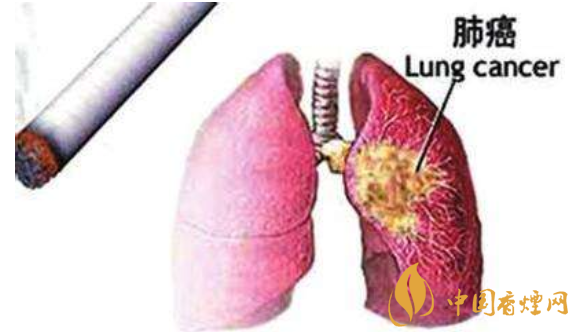

肺癌是生活中大家经常疾病,近年来临床上肺癌患者也是越来越多,谈到患肺癌的原因,人们自然而然会想到吸烟。从世界范围来看,肺癌是恶性肿瘤中死亡率最高的疾病。那么我们吸烟和不吸烟所患的肺癌是一样的么?下面烟吧小编为大家整理介绍吸烟与肺癌的关系研究。

1、吸烟与肺癌的关系:吸烟对健康有害,主要是因为吸烟会大大增加得肺癌的机率,这点毋庸置疑,说道肺癌小编和大家想的一样,第一个想到的是吸烟。的确,吸烟是肺癌最重要的原因,大约90%的肺癌与吸烟有关。吸烟关系最为密切的肺癌是鳞癌。

3、吸烟与不吸烟,得的肺癌是一种吗?很显然,答案是不一样。虽然都叫肺癌,但是却是不同的。

病理类型上:腺癌、鳞癌、小细胞癌、大细胞癌,其中前两种最为多见。而之前谈到的近年不吸烟肺癌患者发病率的增多,主要是病理类型是腺癌。除了这一点之外,更重要的是吸烟者的肺癌和不吸烟者的肺癌在基因突变水平有巨大差异。